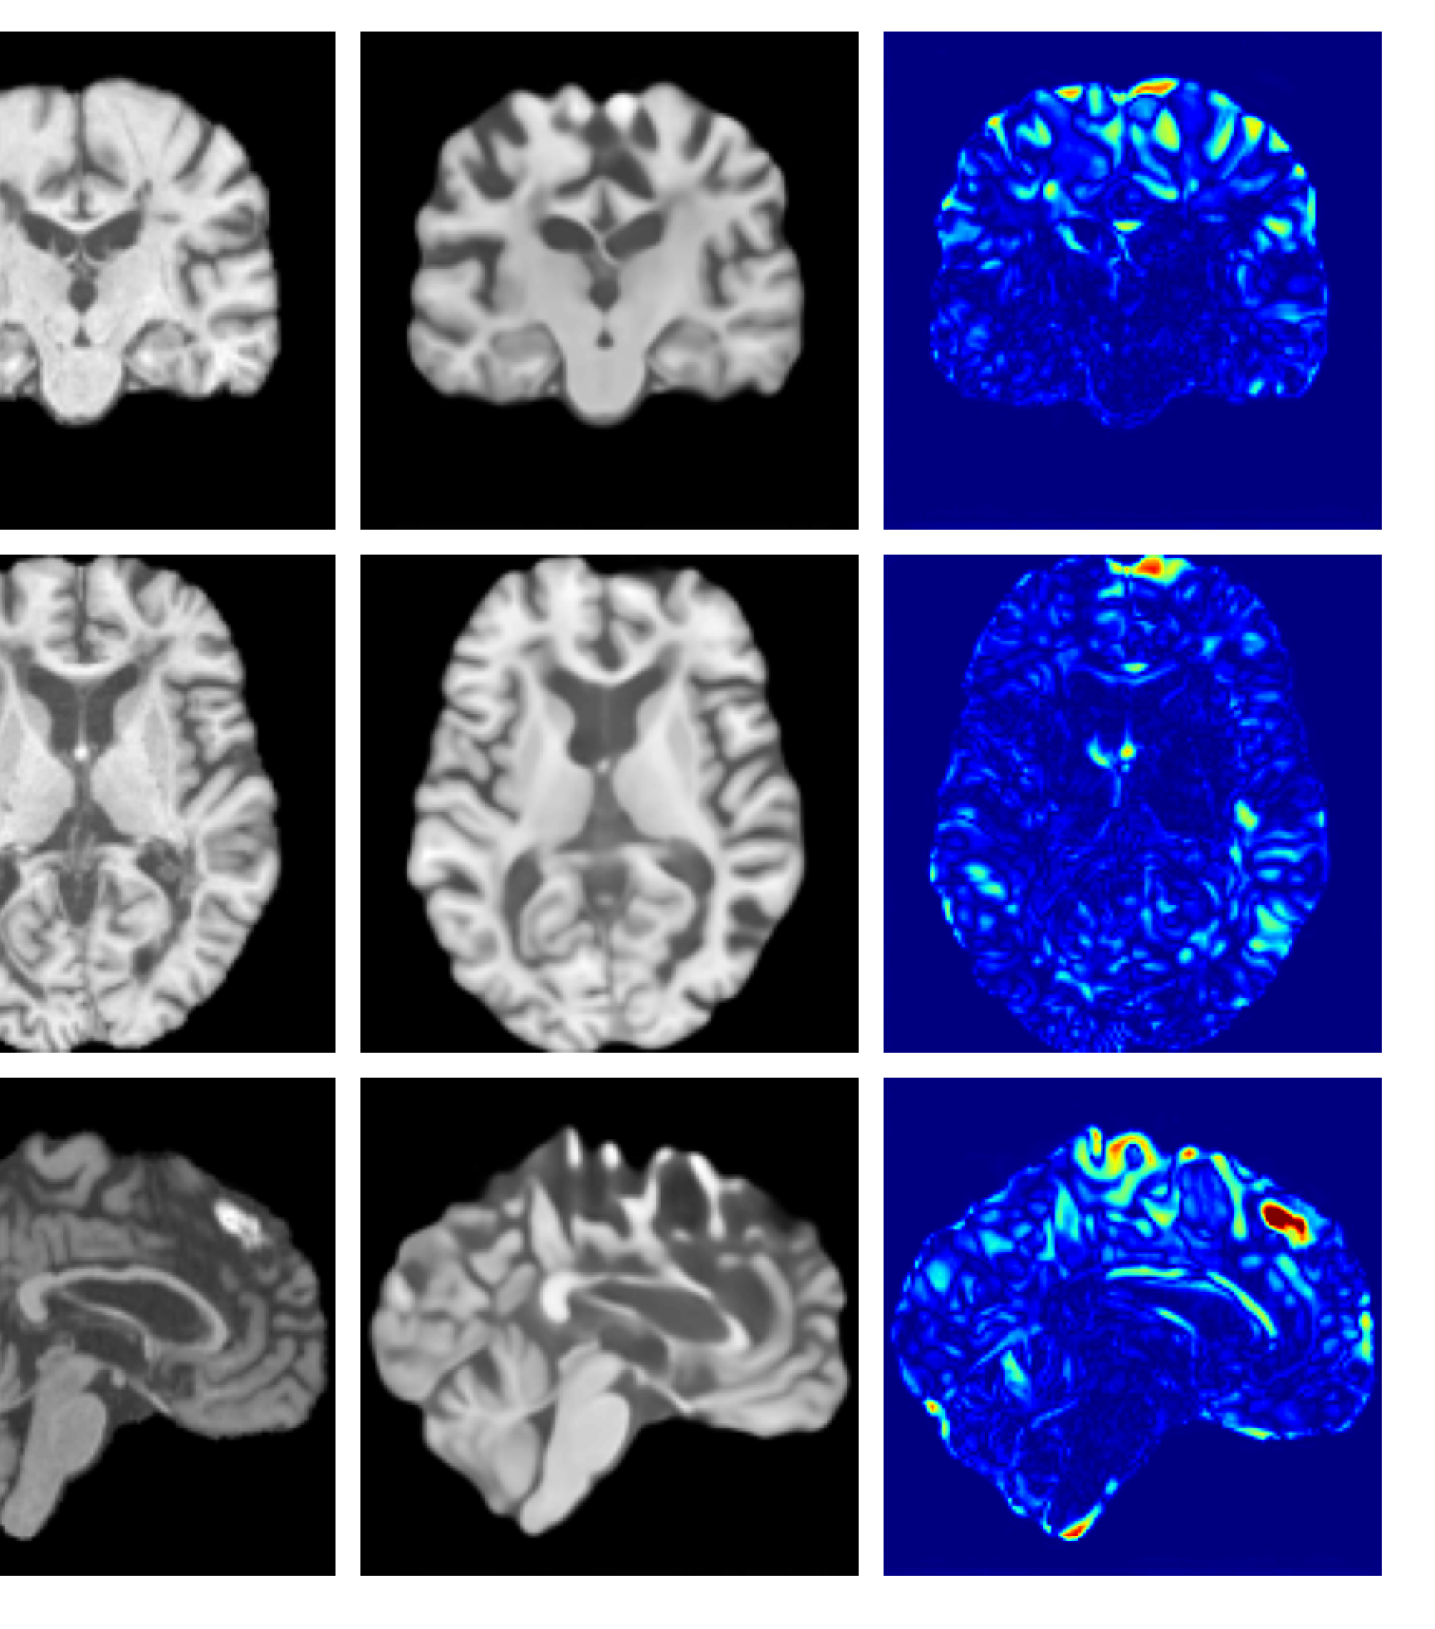

Figures 8 and 9 are enlarged versions of Figures 3 and 4 respectively, with the latter now including results from all compared methods. Figure 10 provides example reconstructions and anomaly maps for an AD subject from the ADNI disease cohort.

Refer to caption

Figure 10: Example reconstructions and anomaly maps for an AD sample from the disease cohort of the ADNI dataset. We expect to see some inpainting of atrophied tissue whilst retaining the defining characteristics of the individual sample.